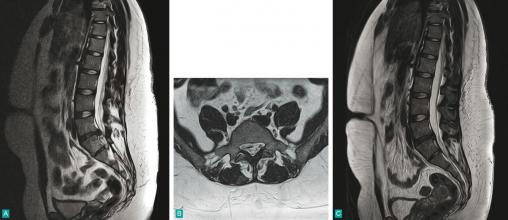

Tomodensitométrie chez une femme de 30 ans :(A) Volumineuse hernie discale rompue avec un fragment exclu ayant migré vers le bas.(B et C) 5 mois plus tard, le fragment exclu a disparu.